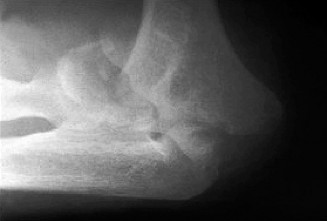

It should be noted that reverse total shoulder arthroplasty is also the procedure of choice in patients with cuff-tear arthropathy (aka rotator cuff arthropathy). Characteristics of cuff-tear arthropathy include superior migration of the humerus due to a massive rotator cuff tear, glenohumeral joint destruction, subchondral osteoporosis, and humeral head collapse (see Fig. 2–17). A reverse total shoulder

Figure 2–17_X-rays of a patient showing evidence of cuff tear arthropathy. The humerus is migrated superiorly, the glenohumeral joint is destroyed, there is subchondral osteoporosis, and the humeral head is collapsed. (From Ecklund KJ, Lee TQ, Tibone J, Gupta R. Rotator cuff tear arthropathy. _J Am Acad Orthop Surg. 2007;15(6):340–349.)